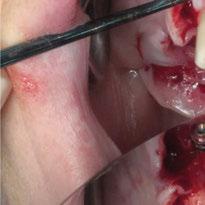

Para ilustrar el proceso, presentamos el caso de una mujer joven diagnosticada de carcinoma adenoide quístico en la región posterior del hemipaladar izquierdo (Figuras 1 y 2). El procedimiento quirúrgico realizado fue una

maxilectomía parcial que incluyó las piezas 24-26 y desde el reborde alveolar hasta la base del cráneo (Figuras 3 y 4). En este caso, la órbita y el globo ocular pudieron ser preservados. La reconstrucción inmediata se realizó mediante un colgajo de músculo temporal homolateral (Figura 5) y el defecto de la fosa temporal fue cubierto mediante una malla de titanio. Posteriormente, la paciente recibió radioterapia (Figuras 6 y 7). 2 años más tarde se diseñó un IS con anclaje en el arbotante nasomaxilar, zona subnasal izquierda

Figura 3. Maxilectomía parcial.

Figura 4. Defecto maxilar tras resección del tumor.